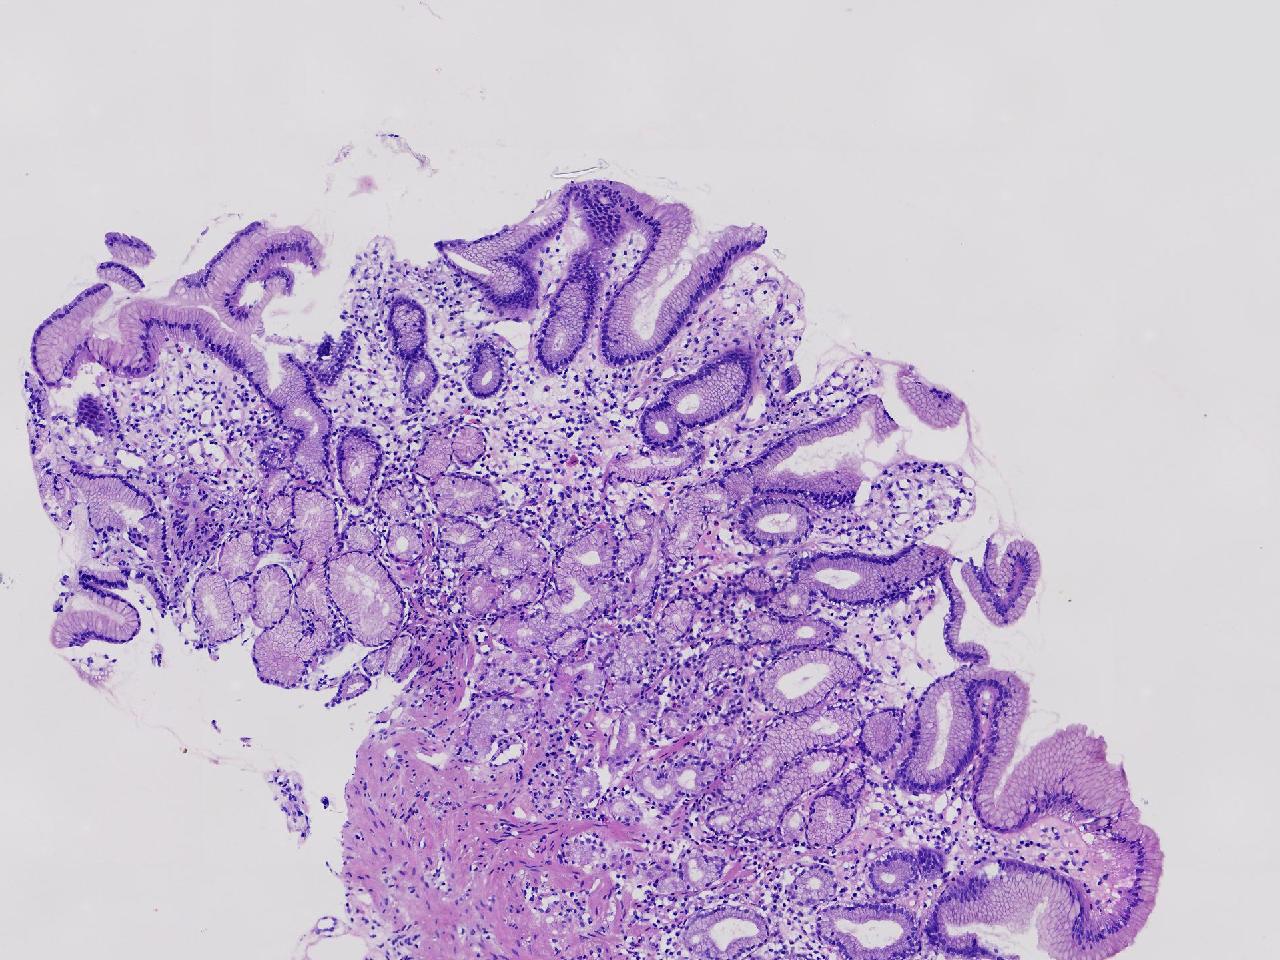

男,76岁。胃体前壁见1纵行溃疡,底覆白苔,周围粘膜充血水肿,于病变周边取材3块。

胃体前壁活检

灰白色不整形软组织3块,直径均0.2厘米。

粘膜中度慢性炎伴糜烂,固有层淋巴细胞聚集